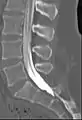

![]() Myelogram showing arachnoiditis in the lumbar spine. | |

Prior to the late 1970s, iofendylate (trade names: Pantopaque, Myodil) was the radiocontrast agent typically employed in the procedure. It was an iodinated oil-based substance that the physician performing the spinal tap usually attempted to remove at the end of the procedure. This step was both difficult and painful and complete removal could not always be achieved. The process of removing the contrast agent necessitated removing some of the patient's CSF along with it and the resulting deficiency of CSF gave rise to severe headache if the patient was raised from the prone position, requiring bed rest in the laying position. Moreover, iofendylate's persistence in the body might sometimes lead to arachnoiditis, a potentially painful and debilitating lifelong disorder of the spine.[3][4] This led to extensive litigation around the world since the substance was administered to millions of myelography patients over the course of more than three decades.[5] After water-soluble agents (such as metrizamide) became available it was no longer necessary to remove the contrast agent as it would eventually be absorbed into the body although the water-soluble agent sometimes gave rise to severe headaches if it got into the head, requiring bed rest in the upright position.